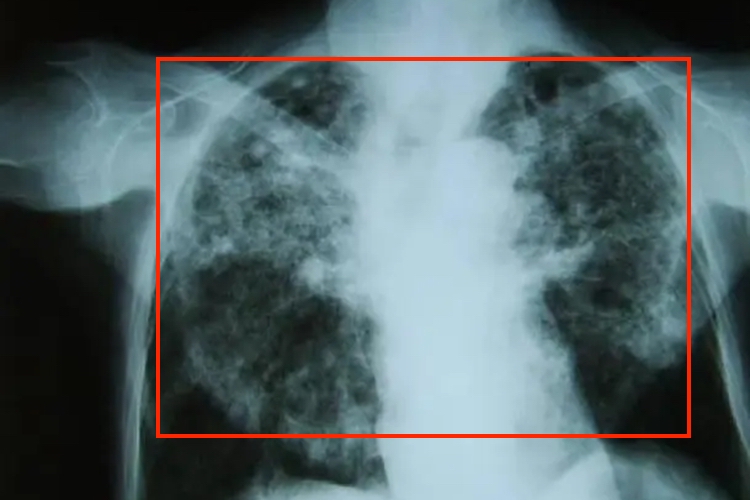

电焊尘肺病是尘肺的一种类型,属于职业性肺病,早期症状不明显,可能会出现咳嗽、咳痰、胸痛、胸闷以及气短的表现。早期咳嗽多不明显,痰量也不多,多数为灰色的稀薄痰。随着疾病的进展,在后期会出现呼吸困难、咯血等症状。电焊尘肺病X线主要表现为肺部结节阴影(直径在1-3mm),网状阴影和大片的融合阴影;其次为肺纹理改变,肺门改变和胸膜改变。